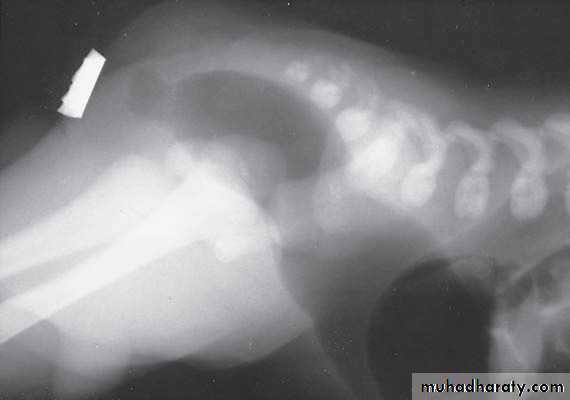

Surgical technique

Low lesion:good long term outlook but tendency to constipation

- A perineal anoplasty =cutaneous fistula.

- anal stenosis &imperforate anal membrane=simple incision &dilatation.

-vestibular fistula =transpositioning anoplasty few monthes later.

High lesion:

- Colostomy at birth.

3-4 month later definitive surgery using posterior sagital anorectoplasty(P.S.A.R.P. pullthrogh) Or penna technique.

- Recently laparoscopic pull through using nerve stimulator to identify anal sphincter ,

-the sphincter is not well developed and nerve supply is deficient= continence not good.- 2 months later colostomy closed.

- Regular anal dilatation.